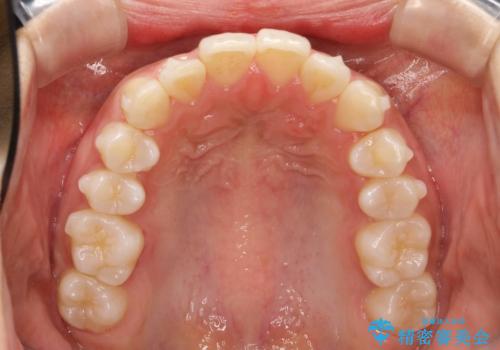

Invisalign インビザラインによる軽度なガタつきの改善

- 奥歯の位置関係はそこまで大きくいじらず、前歯群のみでガタつきの改善を計画しました

奥歯の位置関係に改善の余地はありますが、機能的に問題のない cusp to fossa の関係で咬めているため、前歯のガタつきを前歯のみで改善するというシンプルな計画で、短期間で治療を終了させました。